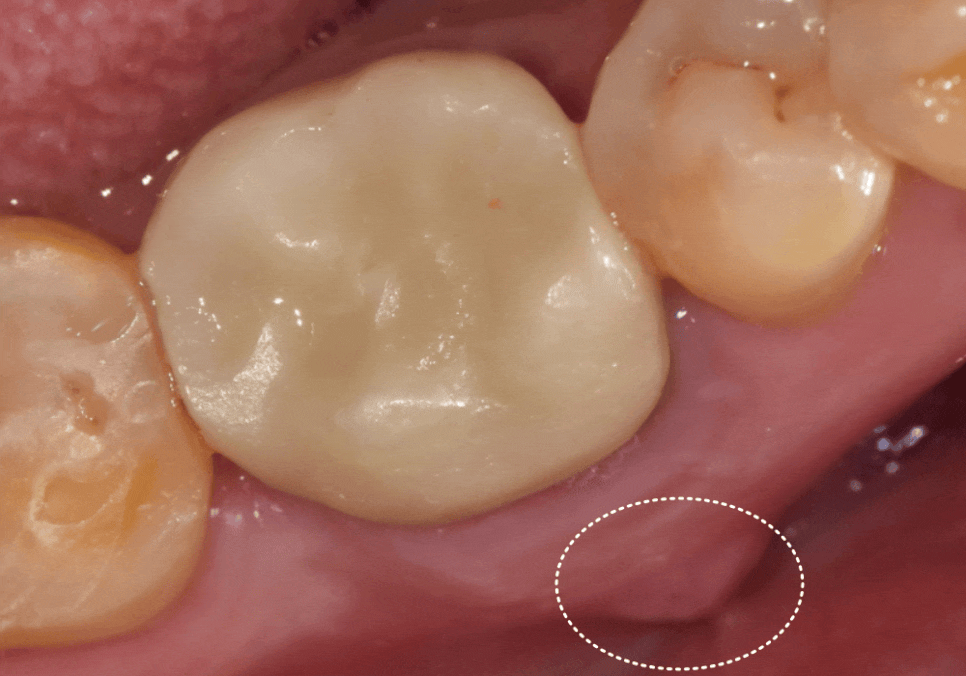

최종 지르코니아 보철을 완성해 드렸습니다.

주변 치아와 조화를 이루며

자연스럽게 마무리된 모습입니다.^^